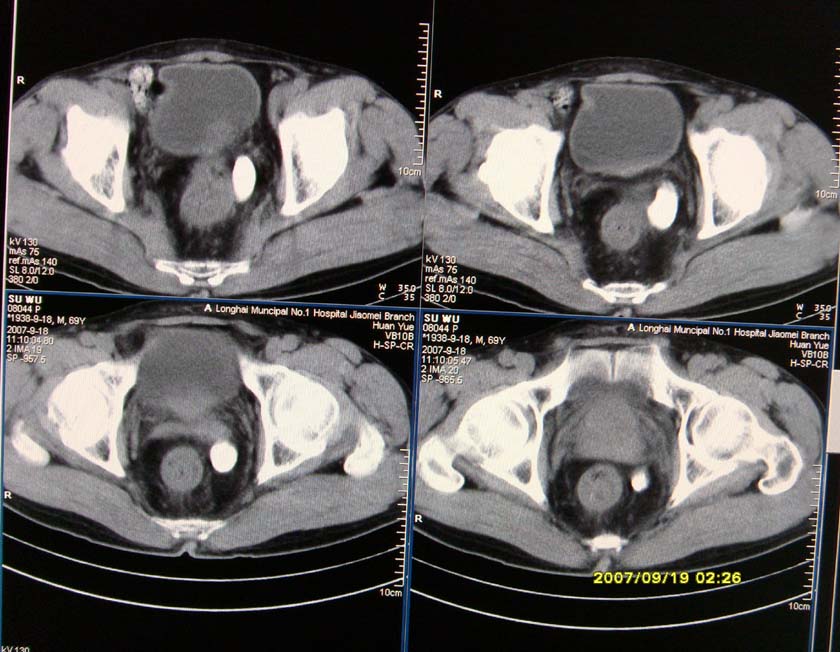

以下是引用xclzq_910在2007-9-19 16:58:00的发言:[br]直肠壁增厚,管腔偏移,直肠癌可能性大

以下是引用宝天曼在2007-9-19 21:11:00的发言:[br]根据直肠壁不规则增厚,考虑直肠肿瘤,不过最后的确诊还是需要肠镜.